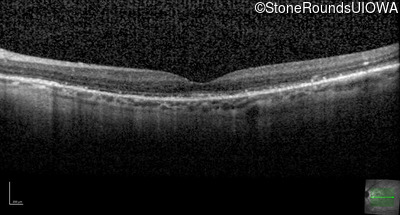

Optical Coherence Tomography - Right - 20/20 -1

Exemplar / OCT Stack

OCT Stack